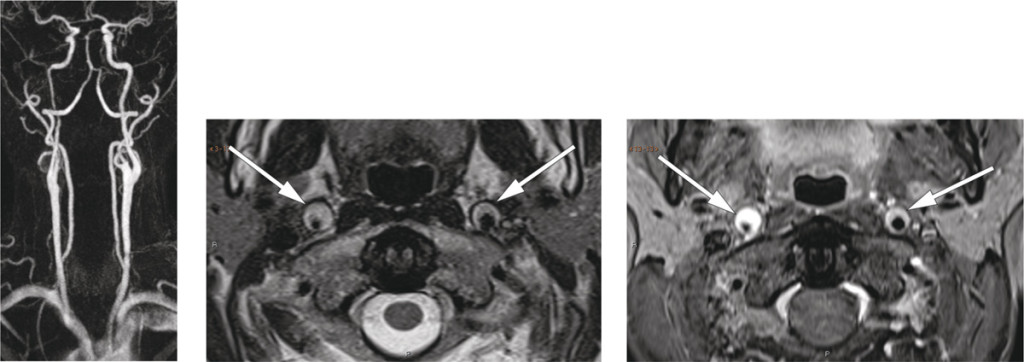

Bilateral carotid artery dissection

The neurological workup revealed Horner’s syndrome. CT angiography showed thickening of the walls of both internal carotid arteries, most pronounced on the right, from just above the bifurcation to the base of the skull. MR angiography and T2-weighted images confirmed bilateral carotid artery dissection, with a minimal lumen diameter of 2 mm on the right side (images to left and centre). Fat-suppressed T1-weighted images (right) showed high signal intensity in the arterial walls, consistent with intramural haematomas.